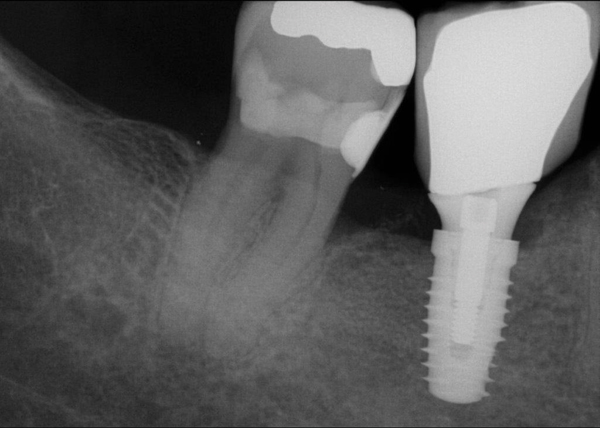

Fig 20. (Case 4) Radiograph of tooth No. 30, which had a hopeless prognosis.

Figure 20

Fig 21. Radiograph of extraction socket. Buccal plate was two-thirds resorbed.

Figure 21